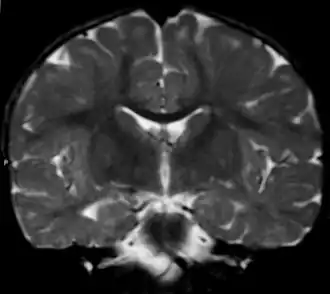

Вид фронтального среза головного мозга при метахроматической лейкодистрофии (МРТ).